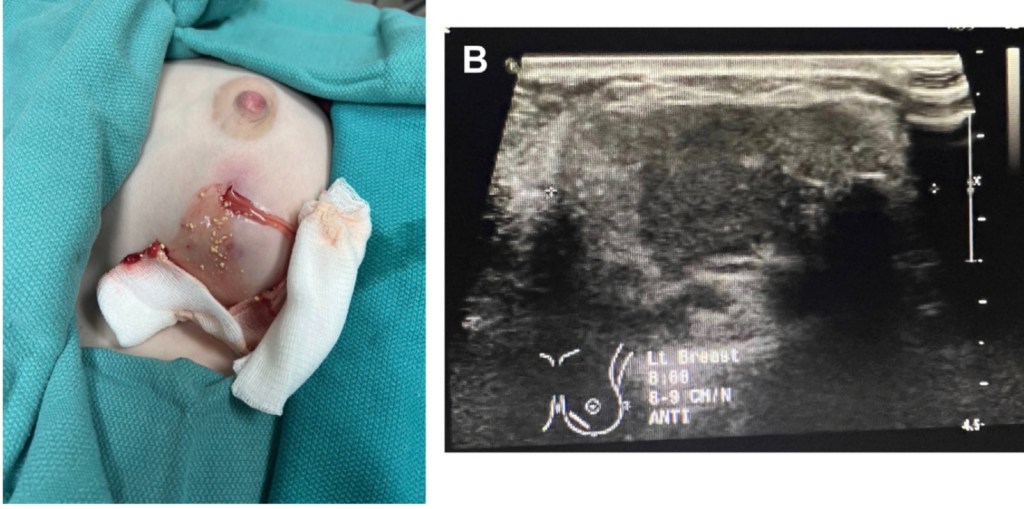

- Unlike simple breast cysts, abscesses and galactoceles in the lactating breast contain breastmilk:

- Which is highly viscous and loculated (Figure):

- Therefore, a needle aspiration alone will likely remove only part of the fluid collection, particularly if it is chronic